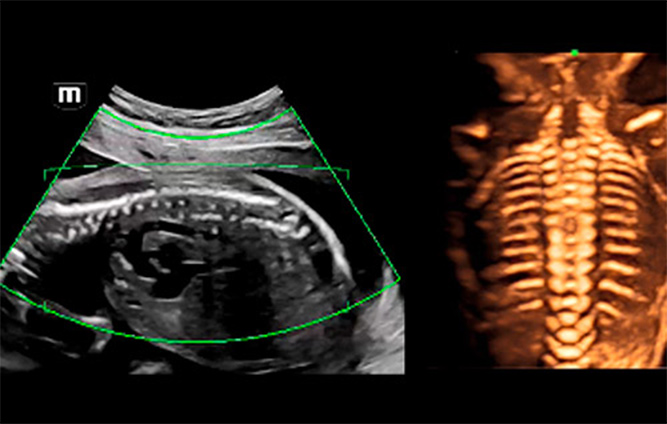

3D/4D-echografiebeelden van de wervelkolom van de foetus